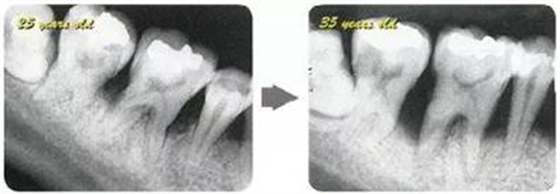

參考病例① 35歲女性

在左下第一磨牙在25歲時(shí)近中處可以看到垂直性的骨吸收,但35歲時(shí)吸收停止,原本沒(méi)有見(jiàn)到的遠(yuǎn)中處骨吸收的,現(xiàn)在卻吸收得很?chē)?yán)重。

在右下處,原本有大量骨吸收的第一磨牙處的吸收卻變緩慢,原本沒(méi)有吸收的第二前磨牙卻出現(xiàn)了吸收。出現(xiàn)吸收的左上第一磨牙的遠(yuǎn)中處,吸收得越來(lái)越多了。

把10年間的變化做成表格。牙周病的發(fā)展根據(jù)各個(gè)人會(huì)不同,即使通一個(gè)人,不同牙齒,不同牙面發(fā)展的狀態(tài)也不同。